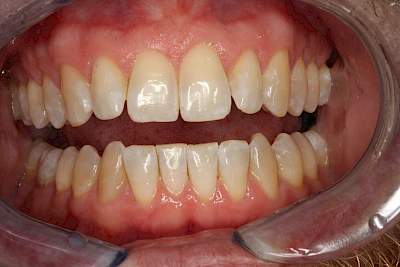

Verfärbungen an Zähnen können außen aufgelagert oder im Zahn eingelagert sein.

Von außen (exogen) eher dunkel gefärbt und meist mehrere Zähne betroffen:

- Genußmittel (Tee, Kaffee, Rauchen)

- Medikamente (z. B. Eisen)

Äußere Verfärbungen durch Genußmittel oder Medikamente (Eisen!) lassen sich meist nur durch den Zahnarzt z. B. mit einer professionellen Zahnreinigung entfernen.